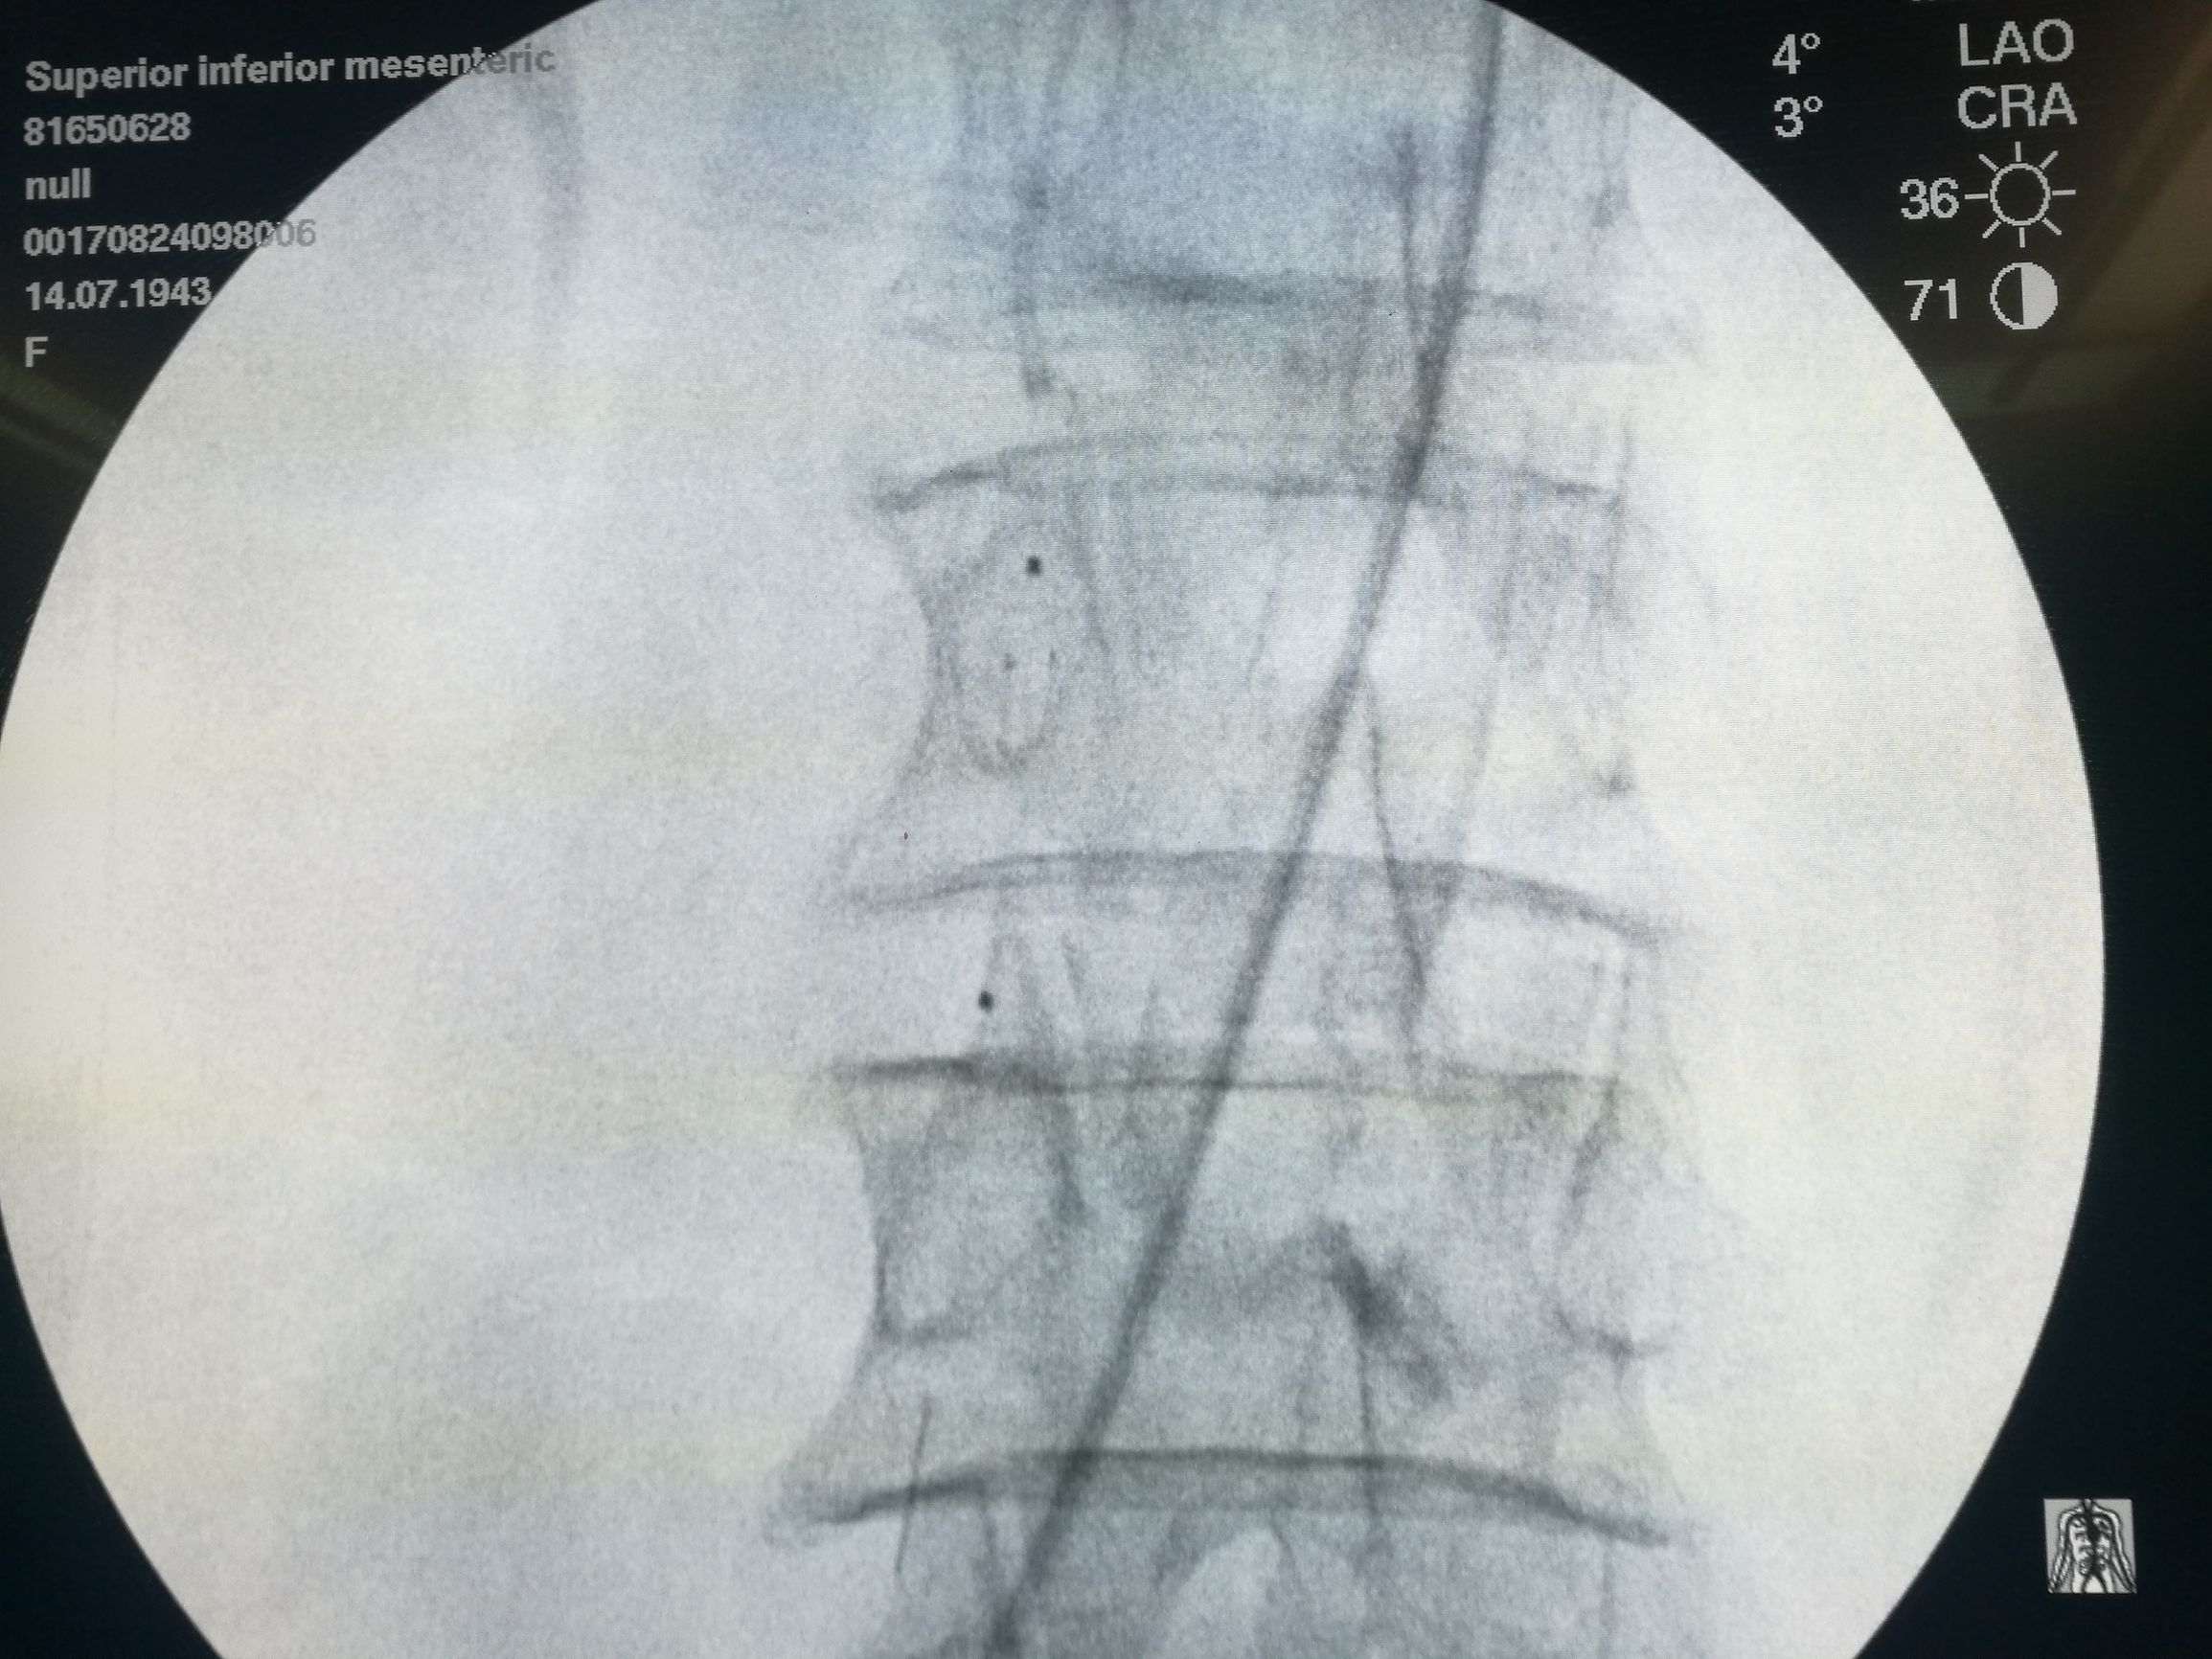

在局麻下经右侧股动脉穿刺,导管选入肠系膜上动脉造影,可见腔内充盈缺损(图3)。

图3. 肠系膜上动脉造影,可见管腔内充盈缺损,局部主干中断